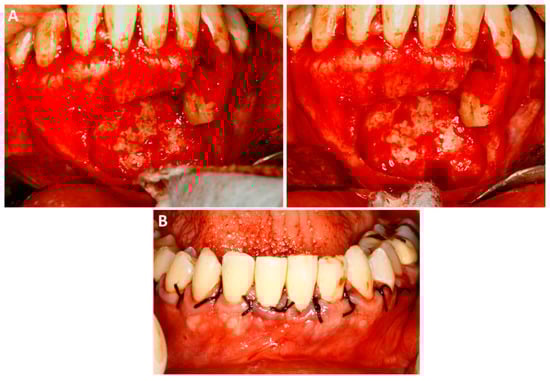

Fifteen months after the second procedure, the panoramic radiograph showed a nearly complete bone neoformation within the surgical site. Clinically, the mucous membranes were found to be intact, with no signs of recurrence. Furthermore, all teeth were in function, without clinical or aesthetic repercussions (Figure 5).

Figure 5. Follow-up of fifteen months after the second procedure. (A)—The panoramic radiograph showed bone neoformation within the entire surgical site, with no signs of recurrence. (B)—Clinically, the mucosa was found to be healthy, and the involved teeth were in function, without functional or aesthetic repercussions.